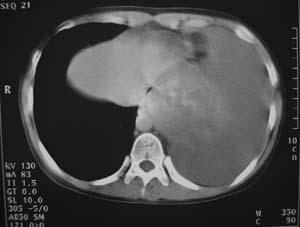

女性,17岁,一年前因股骨病变截肢,现胸憋。

左肺巨大肿块,内散在斑点状高密度骨化影,右肺见多发结节灶,双侧胸膜局限性增厚。有骨肉瘤病史,支持骨肉瘤手术后转移。